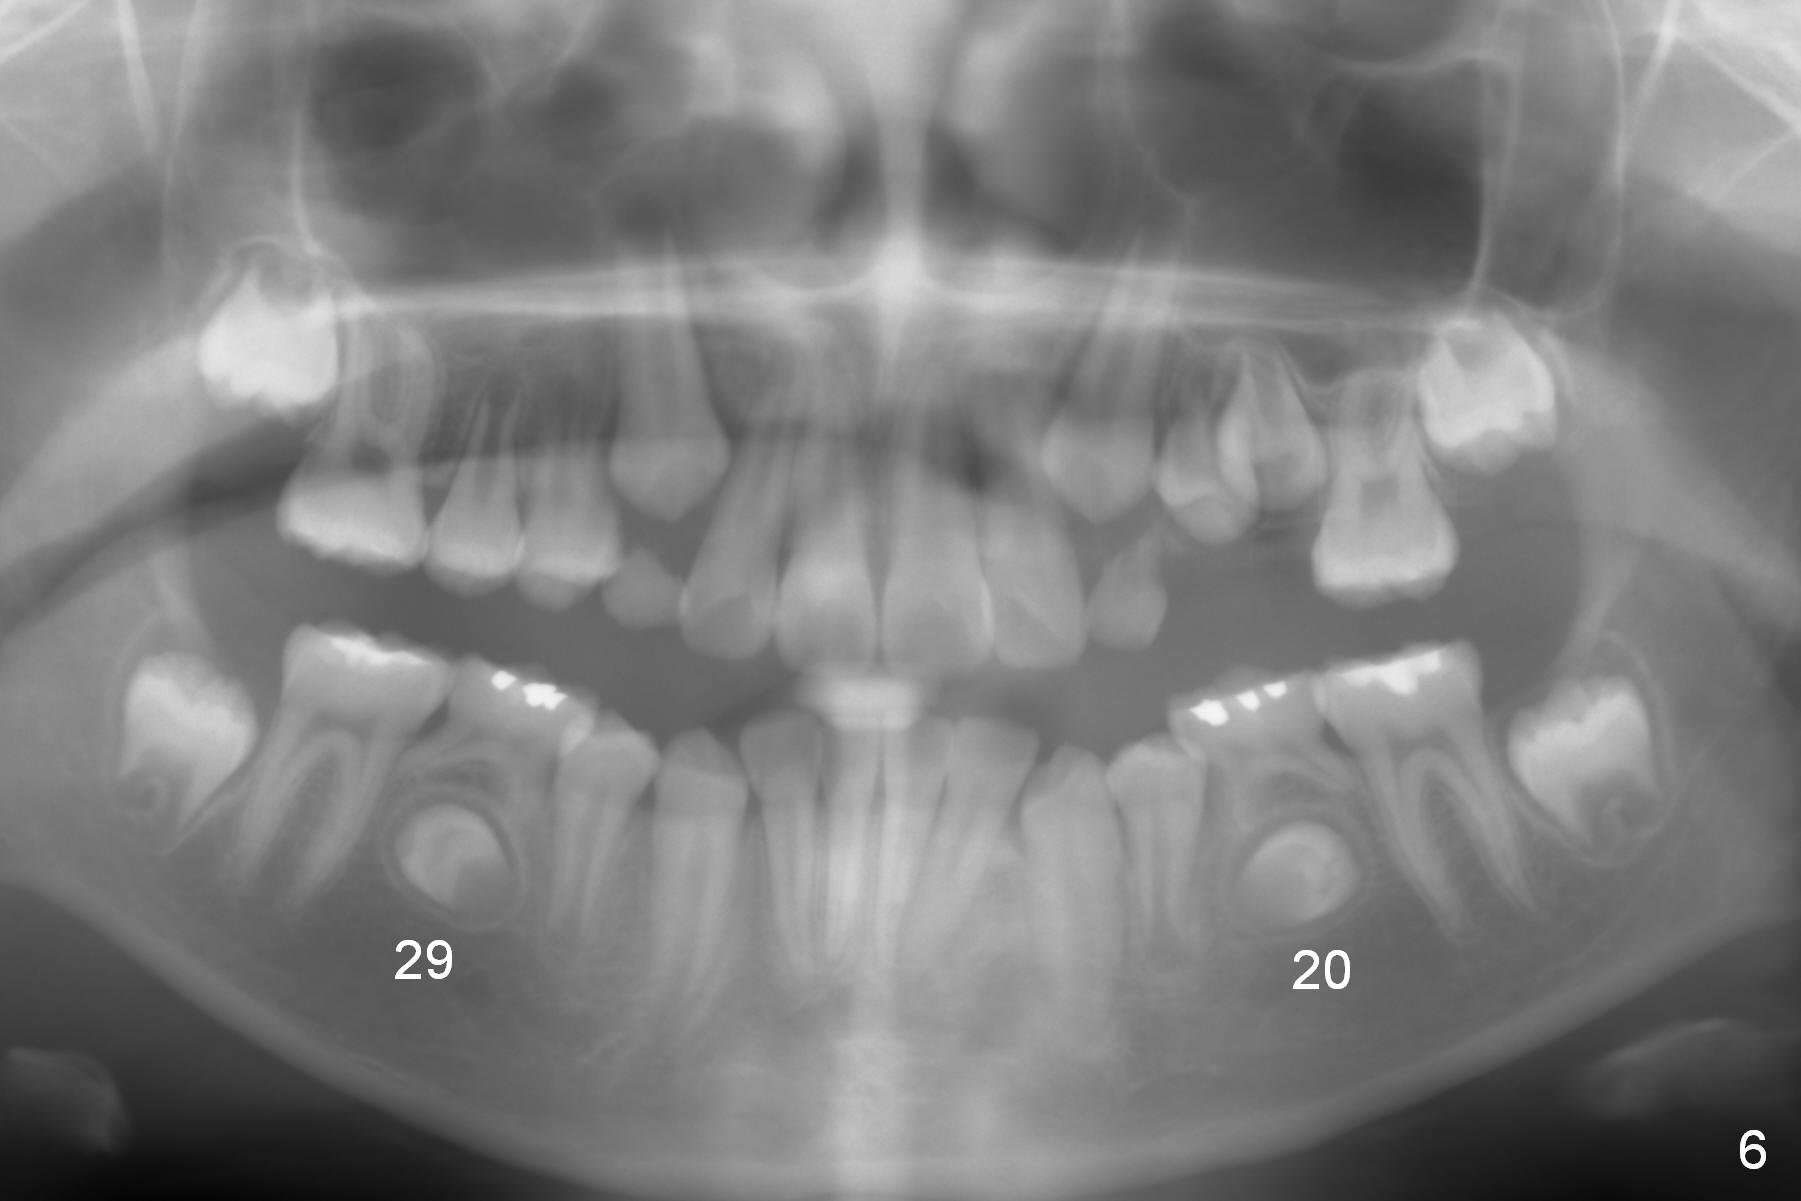

Panoramic X-ray shows underdevelopment of #20 and 29 tooth buds (Fig.6), which is related to K and T being retained (Fig.3). What should be done for K and T as well as 20 and 29?

The patient's mother is 38 years old. She reports that her tooth #20 took long time to erupt. The tooth T remains retained (Fig.7). The patient's 5-year-old sister appears to be normal in tooth bud development (Fig.8).